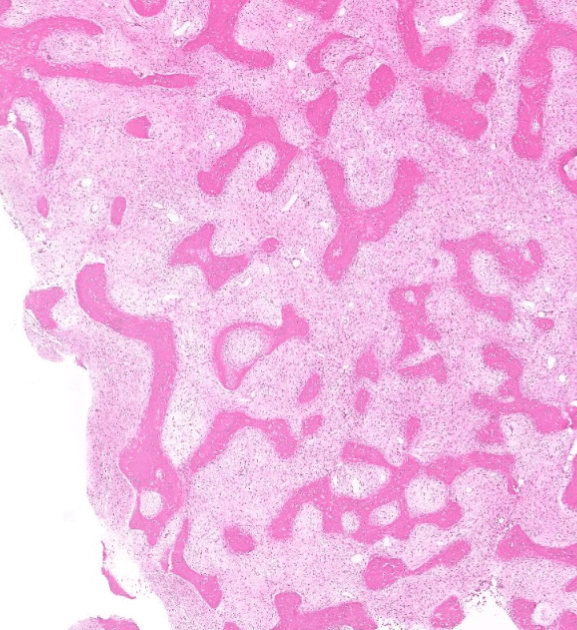

colon cancer